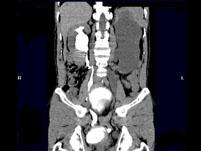

问题 男,55岁,尿频,尿痛伴低热乏力1月。如图所示,下列说法正确的是 ( )

选项 A.左侧输尿管多发性狭窄 B.右侧肾积水 C.膀胱变形 D.左侧输尿管结核 E.左侧输尿管癌

答案 ABCD